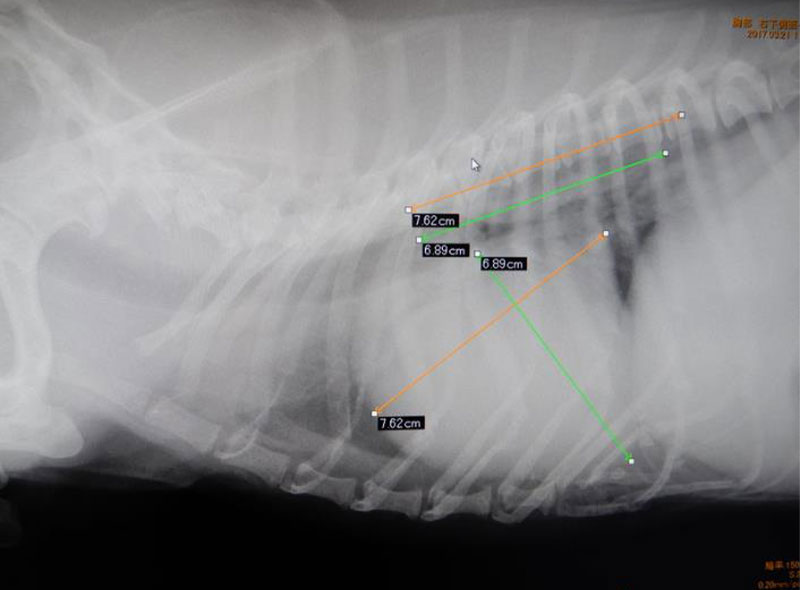

レントゲン検査

通常見ることのできない内臓の大きさや形、配置の変化を調べます。

心臓病、肺や気管・気管支の状態、腹腔内諸臓器の大きさや形の変化、腫瘍や結石の有無などがわかります。

循環器の疾患

僧帽弁閉鎖不全症

犬・中年齢以上・小型犬で見られます。はじめは無症状ですが、進行するにつれ、動悸・息切れから、胸に水が出てきて、呼吸困難になり非常に苦しくなります。

定期検診で、雑音が聴取された場合は、無症状のうちに、検査および必要に応じた早期治療を開始してあげると元気に長生きできます。

胸部レントゲン検査、超音波検査、血液検査(特殊項目)